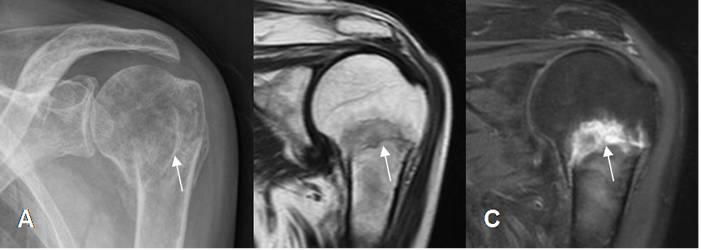

Fig 40. Fractura de húmero.

A: Rx AP, B: RM coronal en T1 y C: RM coronal en STIR. Fractura no desplazada y en sentido transverso, en el cuello del húmero.